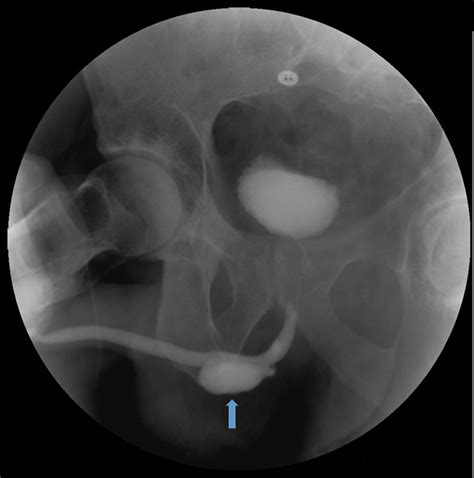

Voiding Cystourethrogram (VCUG) Uses contrast dye to see if the pouch fills during urination.

Urethroscopy Direct visualization of the urethra using a thin camera to locate the diverticular opening.